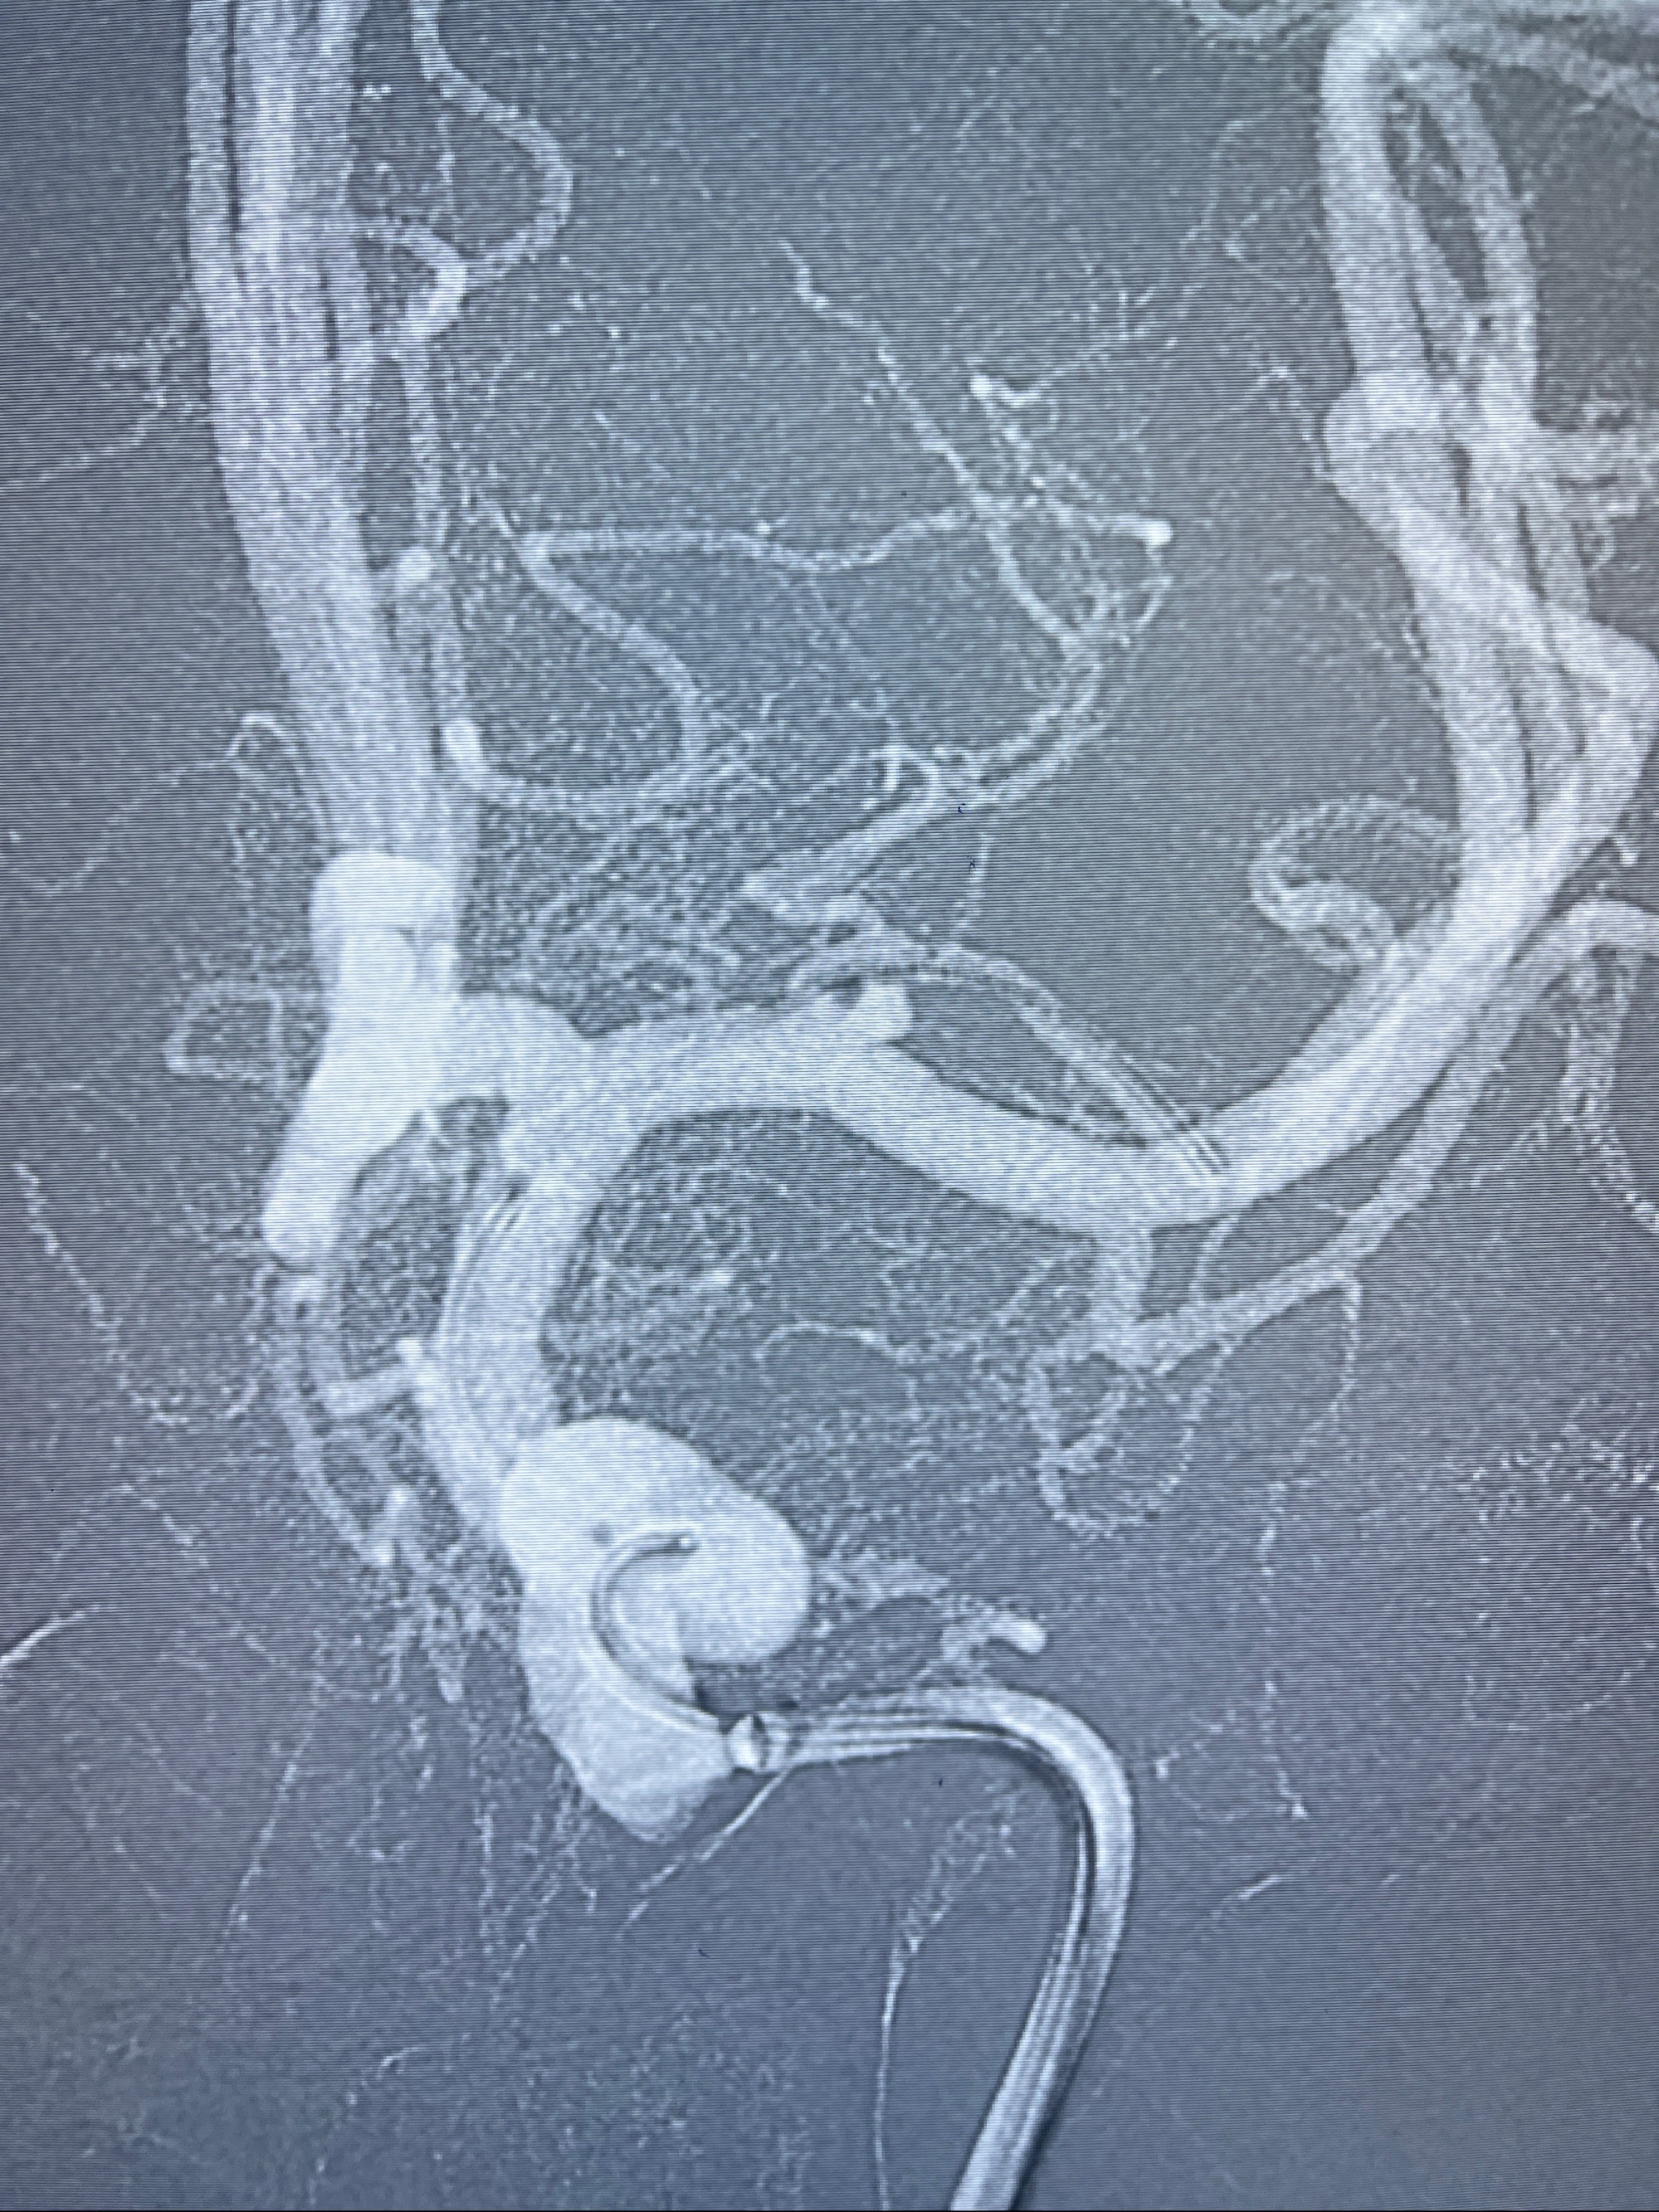

麻醉苏醒佳,遵嘱动作

术后即刻CT